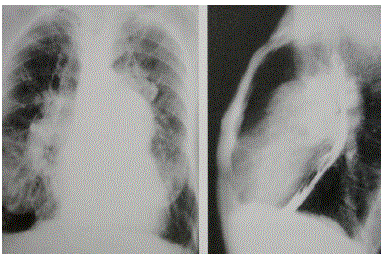

Paciente do sexo feminino, 55 anos, com cianose perilabial e baqueteamento dos dedos realizou estudo com esôfago contrastado para avaliação de disfagia e compressão esofágica.

Baseado nas imagens disponibilizadas, qual o seu diagnóstico?

Paciente do sexo feminino, 55 anos, com cianose perilabial e baqueteamento dos dedos realizou estudo com esôfago contrastado para avaliação de disfagia e compressão esofágica.

Baseado nas imagens disponibilizadas, qual o seu diagnóstico?